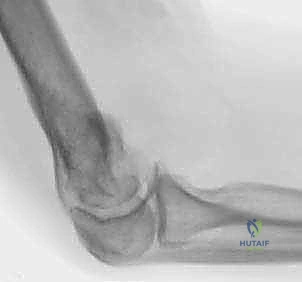

الصور الشعاعية الإضافية والنتائج داخل غرفة العمليات

يحرص الأستاذ الدكتور محمد هطيف على التوثيق الشعاعي الدقيق أثناء وبعد العملية للتأكد من الموضع المثالي للمفصل.